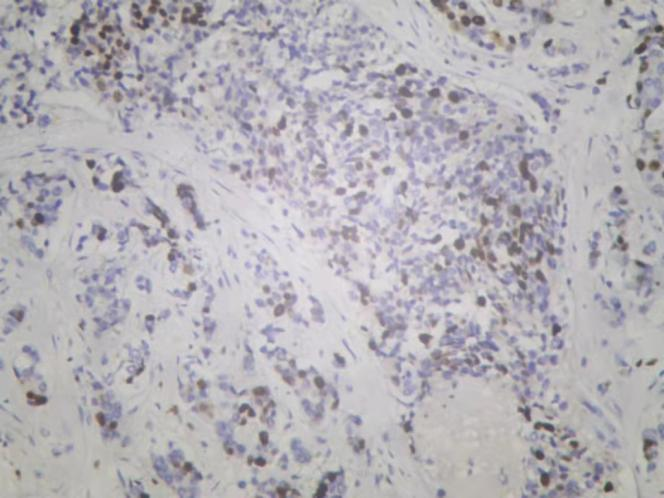

图3. 免疫组化Cerb-B2

图4. 免疫组化PR

图5. 免疫组化ER

图6. 免疫组化Ki-67